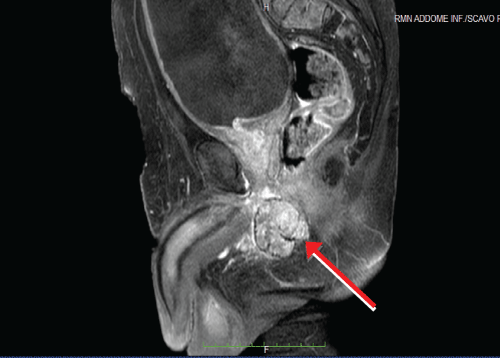

We present the case of a 71-years-old Caucasian male, with a past medical history of hypertension, Benign Prostatic Hyperplasia (BPH) and previous inguinal hernia repair. In November 2002, he underwent a laparoscopic left radical nephrectomy for a 10-cm CRCC of the left kidney with perirenal fatty tissue involvement and thrombosis of the left renal vein (pT3b N0). Patient was followed up regularly on the basis of the EAU guidelines on renal cancer. After a 14-year follow-up he presented a painless, irregular, solid mass of the perineum. MRI scan of the pelvis and perineum revealed a dishomogeneous solid expansive lesion with polylobate profiles of 52 × 58 mm, that originated from the crus of right corpus cavernosum: The mass was placed posteriorly to the base of the penis and strictly related to the internal profile of the right ischiopubic branch with partial compression and dislocation to the left of the anal canal and of the corpus spongiosum of the urethra (Figure 1a and Figure 1b). Moreover, the mass reached the limit of the membranous urethra. A trans-perineal ultrasound guided biopsy of the lesion was performed, and the pathological result showed a metastasis of CRCC. A multi-disciplinary meeting was scheduled. The patients presented favorable prognosis according to Heng and Memorial Sloan-Kettering Cancer Center (MSKCC) criteria and would have benefited from surgical resection of this single metastasis. In order to reduce surgical risk during the exeresis of the mass, the patient was treated with 4 cycles of pazopanib, as presurgical modality. Adverse effects were G1 increase in blood pression and grade 2 diarrhea symptoms. In April 2017, a follow-up-scheduled MRI scan demonstrated volumetric a 30% reduction of the perineal lesion (Figure 2a and Figure 2b). Thus, in June 2017, this patient underwent metastasectomy of the perineal mass by a median perineal access. The mass was smoothly dissected from the corpus cavernosum and the corpus spongiosum of the urethra (Figure 3a, Figure 3b and Figure 3c). The final pathological report revealed metastatic carcinoma from the right corpus cavernosum, compatible with RCC dissemination, and with negative surgical margins. According to complete resection, no TMT was proposed after surgery. At 12-month follow-up, the patient is in general good health status, and total body CT scan showed no recurrences.

Figure 2A: Sagittal MRI scan demonstrated a 30% volumetric reduction of the perineal mass (red circle). View Figure 2A